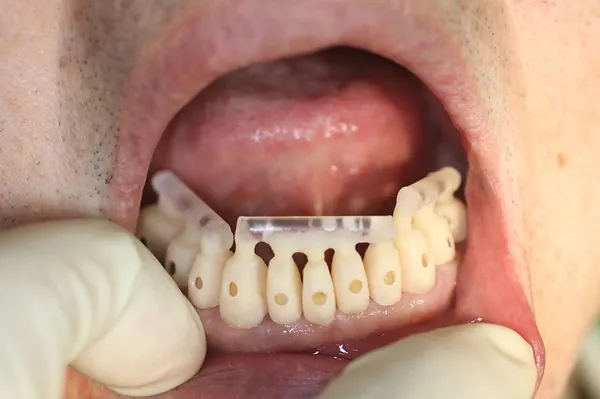

6入れ歯にしないブリッジ治療【ケース3】

このケースの患者さんは上の歯の歯槽膿漏が心配で来院されました。上の歯は11本残っており、下の写真の緑色に囲われた歯を1本抜歯して、計10本の歯を使って端から端まで繋げる治療を行いました。H22.5月に治療が始まり、H23.1月に完成しました。

以下の写真はR4.9月に撮影した写真です。

2022年現在72歳の女性の方です。

治療が終了してから13年経過していますが、今も大丈夫です。